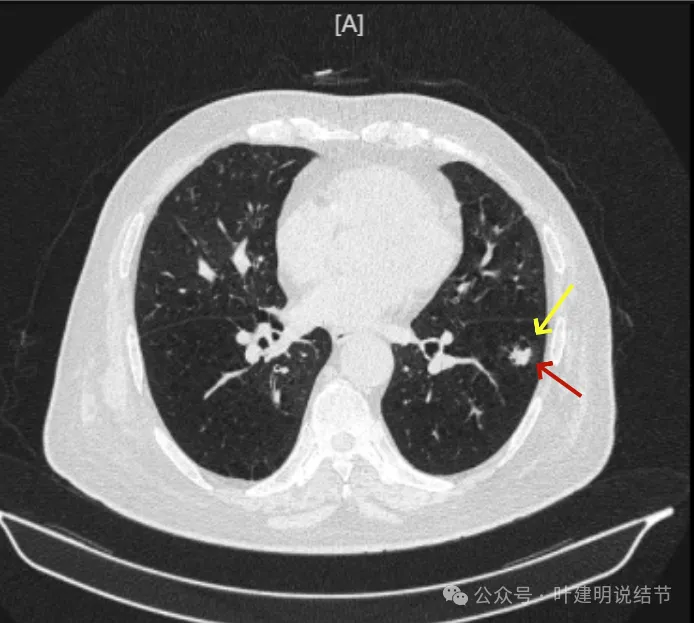

先看2024年6月的影像:

靠叶裂侧密度高、实性,灶内空腔多房,有微小血管走向并进入病灶的囊壁内,叶间裂有受牵拉。

囊壁明显厚薄不均,内壁也不光滑,而整体轮廓与边界却较为清楚。

部分边缘有细毛刺样征、中间密度低些,边上有囊腔,有的地方有少许磨玻璃成分,见到有小血管多处进入病灶。